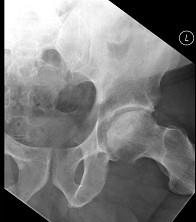

问题 男,47岁,长期左髋痛,请结合CR和MRI片,选择最可能的诊断 ( )

选项 A、暂时性骨质疏松 B、股骨头缺血坏死 C、退变性囊肿 D、骨岛 E、髋关节结核

答案 B